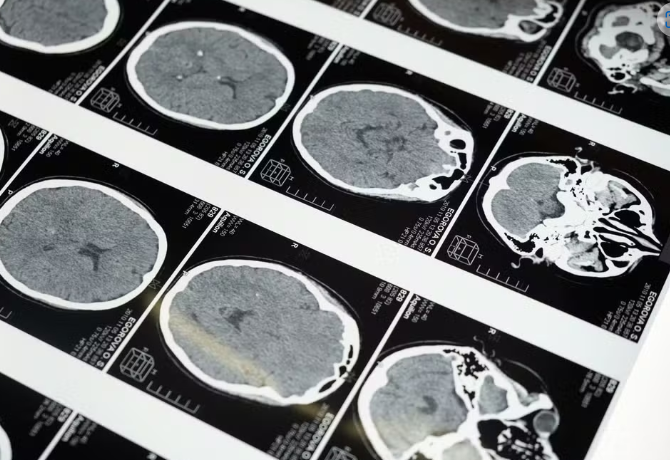

Cientistas descobriram que o estresse agudo induz uma mudança nos sinais químicos dos neurônios — Foto: Daniel Ivanaskas/Arte G1/Arquivo